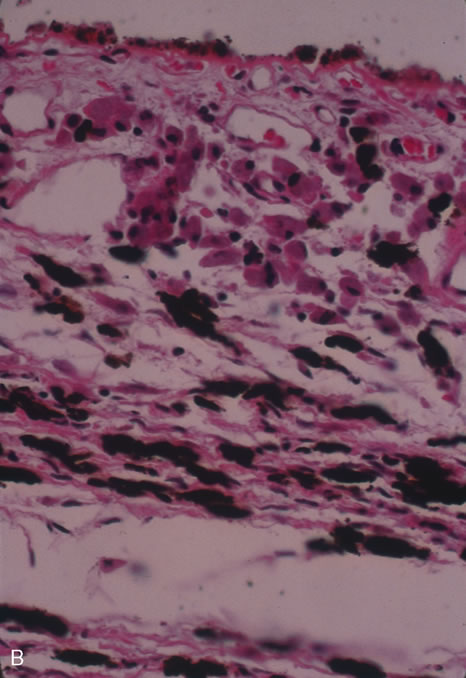

In primary ocular HSV infections, a severe follicular conjunctivitis with regional adenopathy is present. Vesicles may appear on the eyelid skin or lid margin, producing blepharitis (Fig. 3). Corneal involvement initially takes the form of a superficial punctate keratitis, which may progress to dendritic or geographic ulceration. Stromal infiltrates and uveitis are less common and relatively mild in primary disease. In uncomplicated cases, lesions usually heal completely in 2 to 3 weeks without scarring. Most cases of ocular HSV are recurrences. Recrudescent ocular herpes may take the form of dendritic or geographic ulcers, recurrent erosions, interstitial or disciform stromal keratitis, and anterior uveitis.3 HSV may also be an agent of retinitis and acute retinal necrosis (Fig. 4).